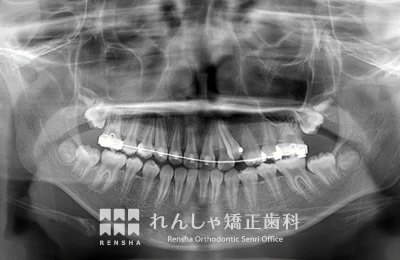

中高生

永久歯列はほぼ完成してしますが、歯列を側方だけでなく後方へも拡大し、埋まっていた右上奥歯を引っ張り出しています。

| 主訴 | 埋まったままでてこない歯がある |

|---|---|

| 診断名 | Angle Class II 小臼歯の埋伏と叢生を伴う上顎前突 |

| 初診時年齢 | 13歳5か月 |

| 装置名 | マルチブラケット装置 |

| 抜歯非抜歯 | 非抜歯 |

| 治療期間 | 2年3か月 |

| 費用の目安 | 約82万円+消費税(検査料金、都度の処置費用等も合わせた総額) |

| リスク副作用 | 歯の移動に伴う軽微な歯根吸収、歯槽骨吸収、歯肉退縮(本症例では軽度の歯根吸収を認めた)、矯正器具装着中のカリエスリスク増大(本症例ではカリエス発生無し) |